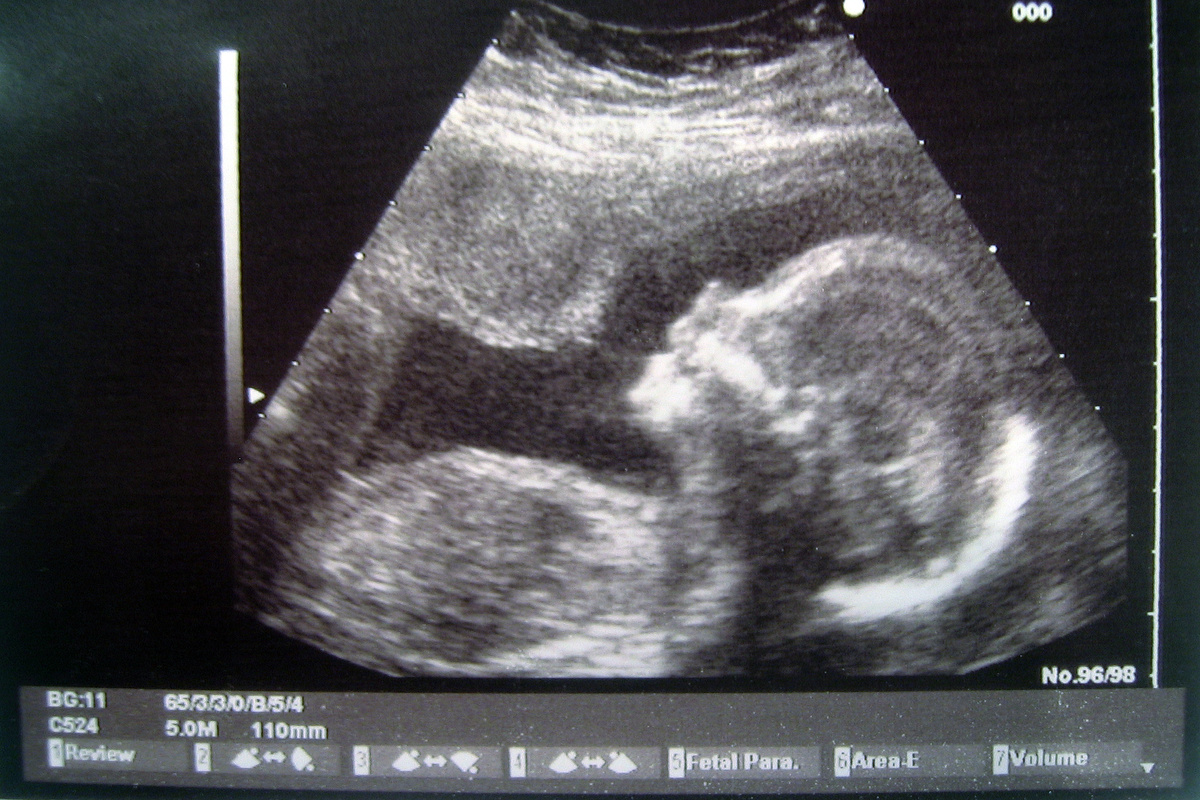

Плод на седьмом месяце беременности

У плода к седьмому месяцу беременности уже сформированы все структуры и системы органов, происходит их подготовка к самостоятельному существованию.

Плод на 7-ом месяц беременности

Также малыш вырабатывает собственный режим сна и бодрствования, и многие мамы начинают замечать цикличность, когда плод наиболее активен, а когда спит.